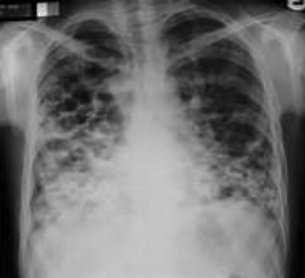

In active pulmonary TB, infiltrates or consolidations and/or cavities are often seen in the upper lungs with or without mediastinal or hilar lymphadenopathy.[1] However, lesions may appear anywhere in the lungs. In HIV and other immunosuppressed persons, any abnormality may indicate TB or the chest X-ray may even appear entirely normal.[1]

7. Other - Any other finding suggestive of active TB, such as miliary TB. Miliary findings are nodules of millet size (1 to 2 millimeters) distributed throughout the parenchyma.